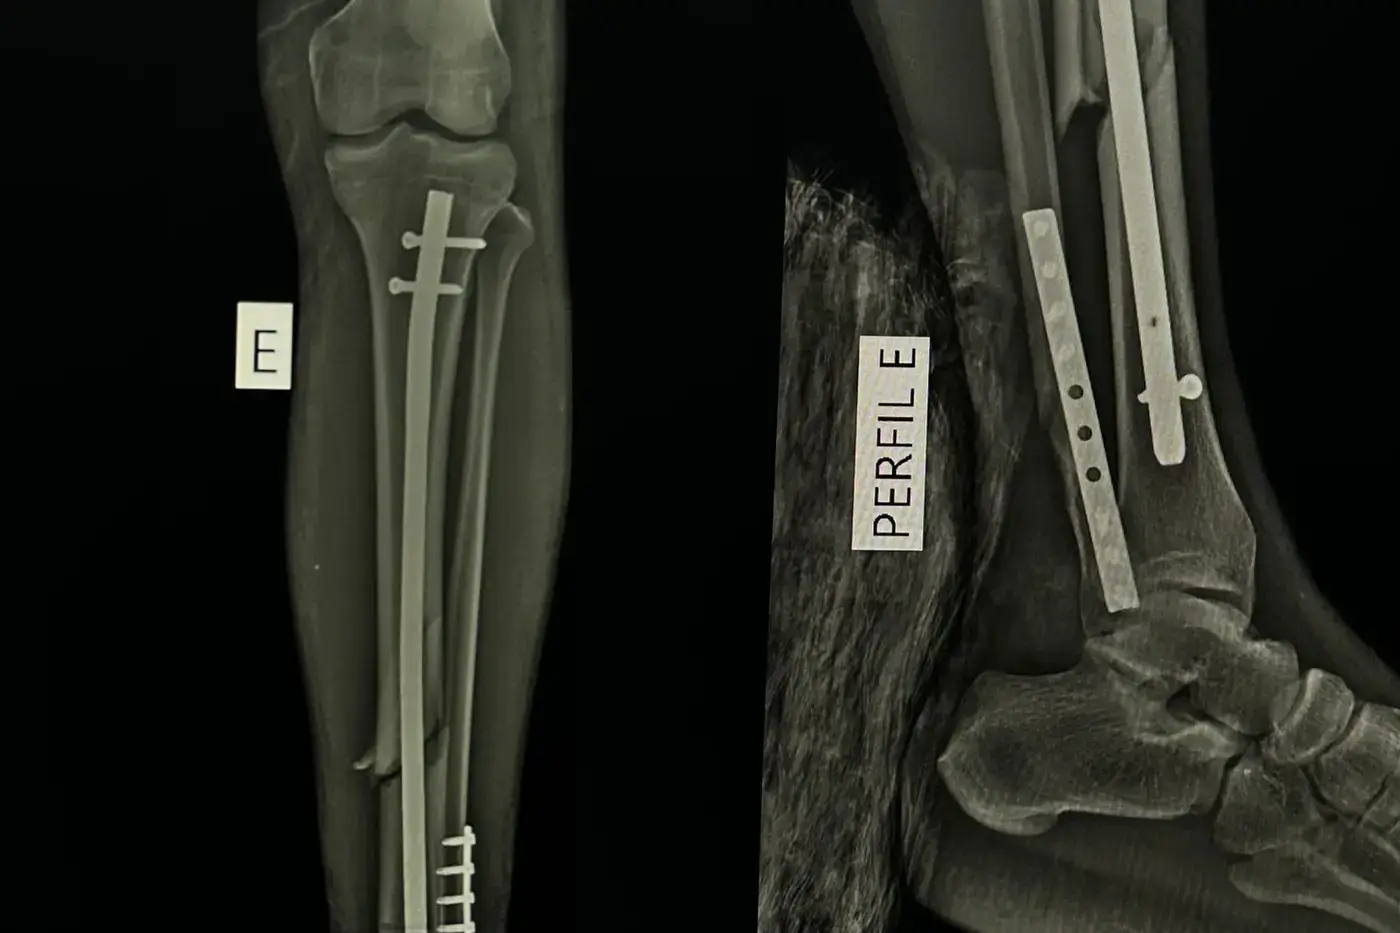

Desde o início da gestão estadual até o ano passado, foram realizados mais de 4.500 procedimentos, com destaque para as cirurgias de fraturas, que lideram as solicitações de atendimento. Em 2024, um total de 1.346 cirurgias foram realizadas pela unidade. Em 2025, a demanda aumentou para 1.479 procedimentos, crescimento considerado dentro do previsto pela direção da unidade.

A estrutura do HELJ tem sido gradualmente ampliada. Desde 2023, o hospital recebeu investimentos do Governo do Amapá, incluindo reforma da unidade, novas salas de atendimento, leitos da maternidade e equipamentos de imagem modernos, como arco cirúrgico, mesa para cirurgia ortopédica, carrinho de anestesia de última geração, além de insumos, como placas e fixadores externos, garantindo um atendimento rápido e eficaz.

Equipamentos de ponta, com arco cirúrgico, possibilitam precisão na imagem óssea durante as cirurgias